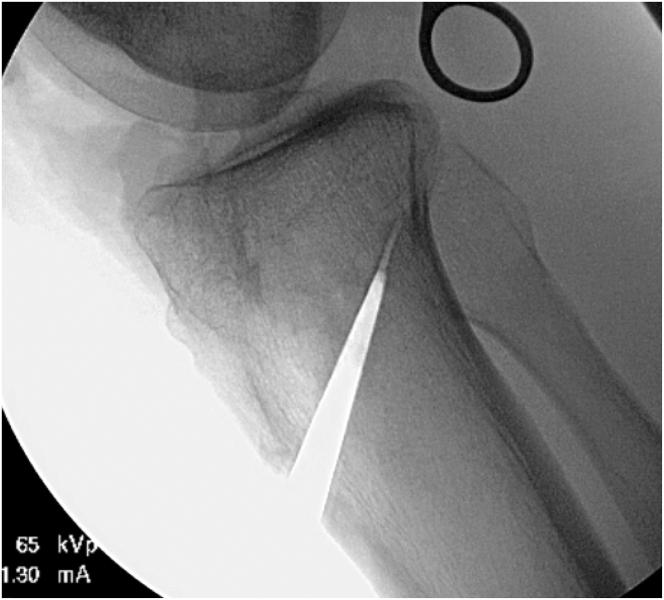

使用吻合器固定的联合全内置前交叉韧带重建术与胫骨前侧闭合楔形截骨术:手术技术

Combined All-Inside Anterior Cruciate Ligament Reconstruction and Tibial Anterior Closing Wedge Tibial Osteotomy Using Staple Fixation: Surgical Technique.

Failure of anterior cruciate ligament (ACL) reconstruction may be associated with a number of technical, anatomic, and patient-related factors. In particular, increased posterior tibial slope is associated with a greater risk of failure after both primary and revision ACL reconstruction, likely a result of increased load across the ACL graft. Surgical treatment of increased posterior tibial slope most commonly involves an anterior closing-wedge osteotomy of the proximal tibia, which may be performed in a simultaneous or staged fashion with ACL reconstruction. The authors describe a technique for combined, single-stage, all-inside ACL reconstruction and anterior closing-wedge osteotomy using staple fixation. The proposed technique provides adequate fixation of the osteotomy while minimizing hardware interference with the ACL tunnel placement and maximizing proximal femoral bone stock.

摘要

前交叉韧带(ACL)重建失败可能与多种技术、解剖和患者相关因素有关。特别是,胫骨后倾增加与初次和翻修ACL重建术后失败风险增加相关,这可能是ACL移植物上负荷增加的结果。胫骨后倾增加的手术治疗最常见的是近端胫骨前闭合楔形截骨术,可与ACL重建同时或分期进行。作者描述了一种使用钉固定的联合单阶段全关节镜下ACL重建和前闭合楔形截骨术的技术。所提出的技术在使硬件对ACL隧道置入的干扰最小化并使近端股骨骨量最大化的同时,为截骨术提供了充分的固定。